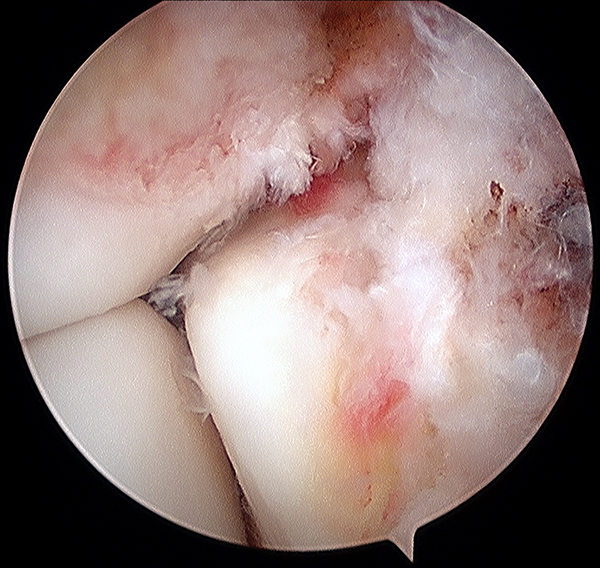

Todos fueron intervenidos quirúrgicamente por el mismo equipo quirúrgico con la metodología protocolizada que se realiza habitualmente en el centro. El procedimiento se realiza, con el paciente en decúbito dorsal, con anestesia raquídea, manguito hemostático colocado en la raíz del muslo, insuflado a 300 mmHg, lavado previo con clorhexidina y embrocado con alcohol ispropílico y clorhexidina. El primer tiempo es artroscópico, efectuado a través de los 2 portales clásicos antero-lateral y antero-medial, sin dispositivos de distracción. Se evalúa la articulación tibio-talar en busca de lesiones asociadas intra-articulares (fig. 1), y se evalúa la ruptura e inestabilidad de la sindesmosis (fig. 2). La diástasis se cuantifica en mm con el palpador (fig. 3). Se considera anormal un desplazamiento mayor a 2 mm. Se clasifica a la lesión como inestable cuando se logra ingresar con la óptica o con la punta del shaver en el espacio tibio-peróneo (abriendo la sindesmosis).

Figura 1: Visualización artroscópica de una lesión de la sindesmosis tibio-peronea inferior.

Figura 3: Lesión condral, hallazgo artroscópico.